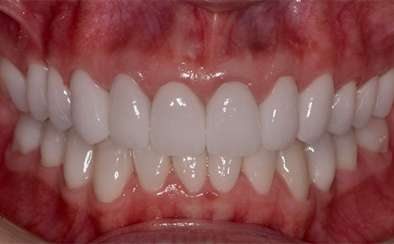

治療前

治療後

なるべく歯を残して、歯の神経も可能な限り保存し残していく方向で治療方法を検討しました。むし歯が大きく神経が侵されている歯は、抜髄を行い、精密根管治療の後にセラミックスクラウンを被せる治療方法を策定しました。患者さんのご希望と了解を得て治療を開始しました。

むし歯治療では、丁寧にむし歯だけを除去して健全な歯質だけを残します。名取歯科医院では、ラバーダムとマイクロスコープの使用が標準です。歯の根と神経の治療(根管治療)も行っていきます。

ラバーダムとはゴム製のシートで、治療する歯だけを露出させるように丁寧に切り取り、お口に装着します。唾液の中には天文学的な数の細菌が存在するため、一度治療した歯が再び悪化して再治療とならないためには、ラバーダムを装着し唾液や細菌に触れないように防湿を施した環境で治療することが何よりも大切で、歯科治療の基本です。歯の根元の黒い部分は膿の溜まった袋です。

むし歯が進行することで歯の神経まで細菌に侵されてしまった場合、昭和型の歯科治療では歯を抜いてしまう抜歯が当たり前でした。しかし、歯を抜いてしまうことで歯並びの乱れなど、ほかの歯への大きな影響があります。そこで自分の歯をできるだけ残すことを考えた「根管治療」や「保存治療」が選択されるようになってきました。

治療後の写真です。きちんと歯の根の治療(根管治療)を施すことで膿の袋も消失します。

歯ぐき(歯肉)の治療も大切です。歯ぐきを健康的な状態に治療していくことで、お口全体を審美的に優れた美しい状態に改善できます。このように歯ぐき(歯肉)の治療を行うことで、炎症を抑え、健康な状態をつくることができます。歯ぐきのコンディションを回復させると同時に、仮歯を入れます。しかしこれは治療中の隙間を埋めたり見た目を取り繕う「仮歯」とは異なります。プロビジョナルレストレーションと言い、最終的な歯(本歯)と同じ形体をもつ歯で、治療した歯や周囲の歯、反対側の歯、歯ぐきなどお口全体の回復と調和を整える大切な治療プロセスです。もちろんこの期間に仮歯での噛み合わせ、咀嚼や嚥下、または発音や発語など機能的な回復に不具合がないか、顎関節への影響や負担がないか検証する期間でもあります。

仮歯で機能回復の確認を行い、そしてさらに微調整を行います。機能的・審美的に改善を確認できた仮歯の形態を元にセラミックスクラウンを作製します。熟練した歯科技工士によるセラミックス制作を行い、装着後に最終的な微調整(咬合調整)を施し、むし歯治療、歯の根の神経治療(根管治療)、白いセラミックスによる修復治療のすべてが終了しました。

| 費用 | ジルコニアセラミック24本:5,280,000円 根管治療(小臼歯5本):770,000円 根管治療(前歯6本):792,000円 合計:6,842,000円 |